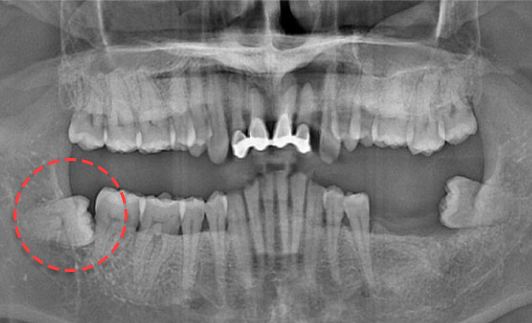

• BEFORE

왼쪽 하악 매복 사랑니 발치 Before X-Ray

치료시작일

2020.05.24

AFTER

왼쪽 하악 매복 사랑니 발치 After X-Ray

치료종료일

2020.06.29

왼쪽 하악 매복 사랑니 발치